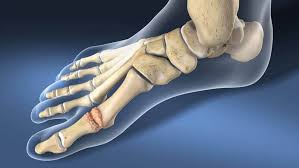

Występowanie tego schorzenia u członków rodziny znacznie zwiększa szansę rozwoju omawianej choroby u przyszłych pokoleń. Warto jednak zaznaczyć, że predyspozycje genetyczne nie zawsze kończą się chorobą sztywnego palucha. Schorzenie może być też wywołane nieprawidłowościami w budowie stawu oraz kości śródstopia. Chodzi tu o kształt powierzchni stawowej oraz o nieprawidłową budowę głowy I kości śródstopia. Wśród innych przyczyn wymienia się nadmierną długość palucha, chorobę Charcota, dnę moczanową, choroby reumatyczne, czy też jałową martwicę głowy pierwszej kości śródstopia.

W sytuacji gdy leczenie sztywnego palucha metodami nieinwazyjnymi nie przyniosło pożądanych rezultatów można wykonać zabieg chirurgiczny. Należy jednak pamiętać, że operacja palucha to rozwiązanie ostateczne, które nie daje 100% gwarancji wyleczenia i wiąże się ze żmudną rehabilitacją. Metody leczenia operacyjnego sztywnego palucha to: